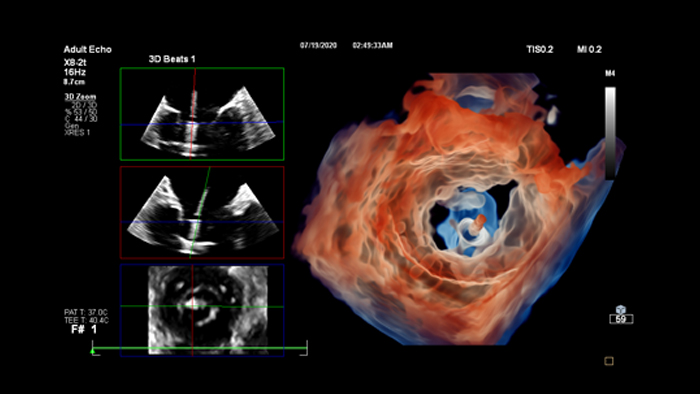

Philips Cardiovascular Ultrasound

The EPIQ CVx and Affinity CVx, our dedicated cardiac ultrasound solutions help to enhance diagnostic confidence and clinical efficiency through superior image quality, advanced quantification tools and automation.

Philips Advanced Visualization Workspace

Review, analyze and quantify clinical information from different modalities and for various clinical indications with AI-enabled 3D models, maps and other quantitative tools.